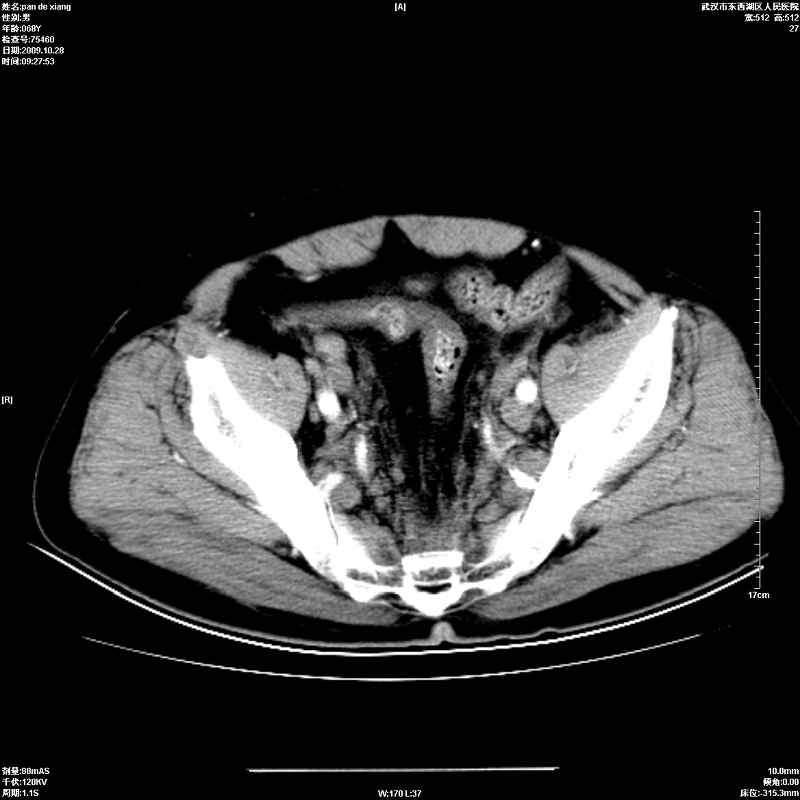

以下是引用杀毒软件在2009-10-28 20:41:00的发言:[br]结合临床考虑---白血病双肾改变或淋巴瘤。

以下是引用zxl51642在2009-10-29 9:59:00的发言:[br]结合临床“单克隆免疫球蛋白血症”,考虑双肾为继发损害并肾功能不全(尿中大量igg及少量iga、igm等大分子免疫球蛋白滤出所致继发损害),椎前软组织肿块为髓外造血。与浆细胞瘤有区别,平扫时有战友说的很清楚。